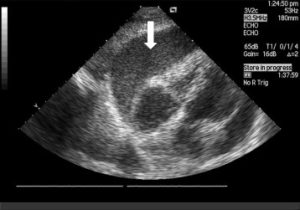

Connected devices leveraging AI capabilities are now being deployed in the fight against the leading cause of death in the U.S.: heart disease. Placing the power of AI-enabled cardiac ultrasounds in the hands of nurses and other health professionals is saving lives, revitalizing patient experiences, and contributing greatly to the broadening scope of connected healthcare potential.

The market for new connected solutions has never been better, what with the downward trend of in-person doctor visits, a dearth of qualified sonographers, and a huge population of aged individuals. Solutions demonstrating the power and reach of AI such as cardiac ultrasounds are a reassuring harbinger of the future of connected healthcare.